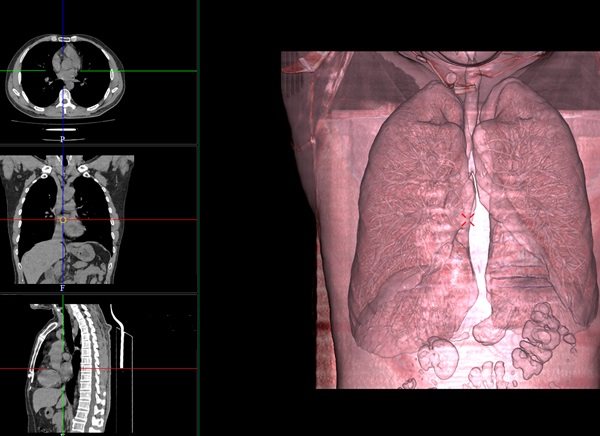

图像浏览

多平面重建